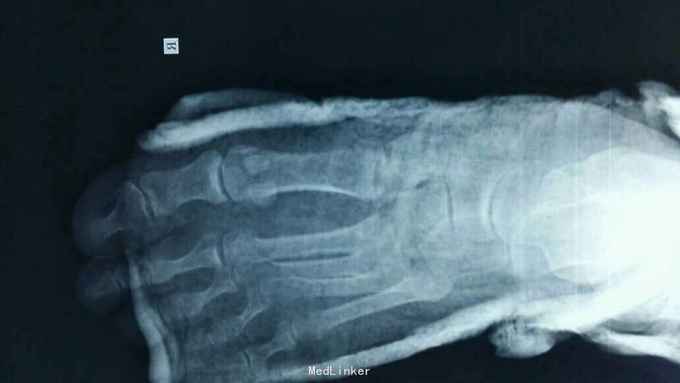

主诉:右足外伤后肿痛,活动受限11天。 现病史:患者于2015年11月10日摔伤右足,当即肿痛,活动受限,急去当地医院拍片及入院行石膏固定保守治疗,效果不佳,为求进一步治疗来诊我院,经门诊阅片及查体后以“右足多发骨折,脱位,韧带损伤”为诊断收入院。

查体:右足略肿胀,畸形明显,足背压痛广泛阳性,可触及骨擦音及骨察感,活动受限,末梢各趾活动自如,足背动脉清。 辅助检查:大致正常。

诊断:右足多发骨折伴跖跗关节脱位,韧带损伤 治疗:患者入院后,完善检查,于2015年11月25日行手术治疗,现切口愈合良好。